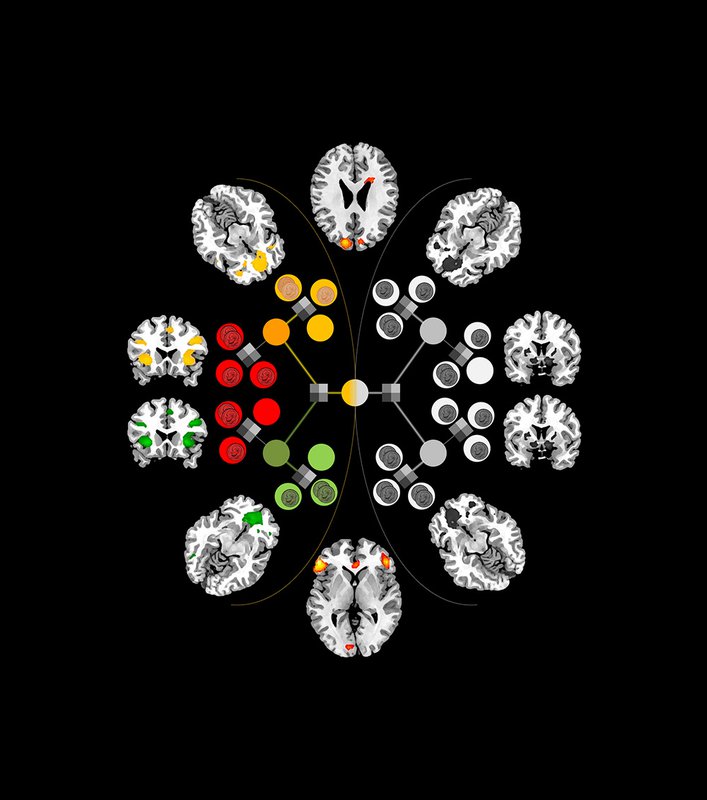

Researchers at the California Institute of Technology (Caltech) have, for the first time, pinpointed areas of the brain—the inferior lateral prefrontal cortex and frontopolar cortex—that seem to serve as this "arbitrator" between the two decision-making systems, weighing the reliability of the predictions each makes and then allocating control accordingly. The results appear in the current issue of the journal Neuron.

With the results from those tests in hand, the researchers were able to compare the fMRI data and choices made by the subjects against several computational models they constructed to account for behavior. The model that most accurately matched the experimental data involved the two brain systems making separate predictions about which action to take in a given situation. Receiving signals from those systems, the arbitrator kept track of the reliability of the predictions by measuring the difference between the predicted and actual outcomes for each system. It then used those reliability estimates to determine how much control each system should exert over the individual's behavior. In this model, the arbitrator ensures that the system making the most reliable predictions at any moment exerts the greatest degree of control over behavior.

In line with previous findings from the O'Doherty lab and elsewhere, the researchers saw in the brain scans that an area known as the posterior putamen was active at times when the model predicted that the habitual system should be calculating prediction values. Going a step further, they examined the connectivity between the posterior putamen and the arbitrator. What they found might explain how the arbitrator sets the weight for the two learning systems: the connection between the arbitrator area and the posterior putamen changed according to whether the goal-directed or habitual system was deemed to be more reliable. However, no such connection effects were found between the arbitrator and brain regions involved in goal-directed learning. This suggests that the arbitrator may work mainly by modulating the activity of the habitual system.